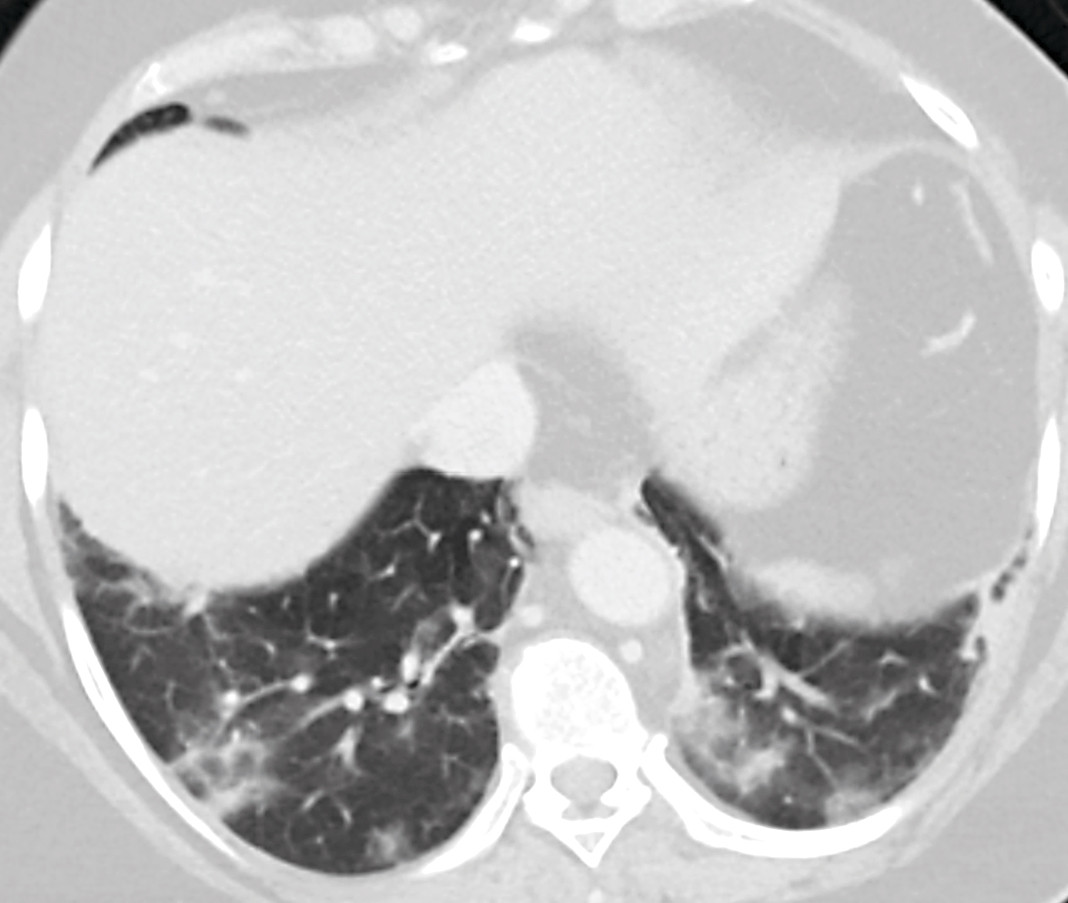

Enkelte pasienter med covid-19 debuterer imidlertid med andre symptomer. I løpet av de siste to ukene har vi i vårt akuttmottak hatt ytterligere fem pasienter med tilsvarende symptombilde, der covid-19 har blitt bekreftet ved sanntids-PCR. Det dominerende symptombildet hos alle disse var magesmerter, der enkelte også hadde smerter i nedre del av buken. I tillegg rapporterte de om nedsatt matlyst, kvalme og oppkast. Noen hadde også diaré. Ingen hadde nytilkomne luftveissymptomer. Alle ble utredet med CT abdomen som ledd i utredningen av magesmerter, der bildene viste typiske funn for covid-19 i lungene (figur 2).

Det ble rekvirert en ultralydundersøkelse av lever og galleveier, men ettersom pasienten var overvektig og flere radiologer var i karantene på grunn av den pågående koronaepidemien, valgte man å endre dette til en CT-undersøkelse med intravenøs kontrast. Ved CT av abdomen og bekken ble det ikke påvist aktuelle funn i buken, utenom gallestein som var kjent fra tidligere. Det var ingen radiologiske tegn på kolecystitt. På basale lungesnitt ble det imidlertid sett løst mettede fortetninger perifert i begge lunger samt enkelte områder med mer konsolidert preg. Det var ingen pleuravæske. Radiologen vurderte at funnene kunne passe med viral eller atypisk pneumoni (figur 1).